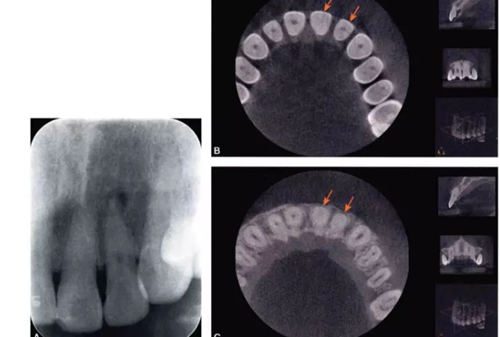

(一)X線診斷

完全鈣化根管在X線片上的表現(xiàn)是根管影像模糊,密度增高,根管密度與周圍的牙本質(zhì)密度接近,甚至無法區(qū)分根管與牙本質(zhì)的影像。有些根管,可表現(xiàn)為根管影像時(shí)斷時(shí)續(xù)或模糊不清,為不完全鈣化根管表現(xiàn)(圖4-1A)。細(xì)小根管的病例在X線片上,根管影像隱約可見,與同名牙或鄰牙相比,根管較為細(xì)小影像清晰度降低。

(二 )CBCT診斷

錐形束CT(CBCT)能重建根管的三維結(jié)構(gòu)從冠狀面矢狀面及橫斷面三個(gè)面連續(xù)觀察根管的解剖結(jié)構(gòu)、走向及鈣化情況。

目前,小視野CBCT物理層厚可達(dá)76m,對(duì)根管系統(tǒng)的顯示明顯優(yōu)于其他影像學(xué)手段。觀察根管的CBCT圖像,冠根向橫斷面能夠比較直觀地顯示根管中央的鈣化情況。觀察時(shí)可從髓底開始,將橫截面斷層由冠方向根尖方向推移,逐層觀察。正常根管位于牙根的中央部位,呈圓形或橢圓形暗影,與周圍的牙本質(zhì)所顯示的致密白色影像有明顯區(qū)別。細(xì)小鈣化根管表現(xiàn)為橫截面中央的暗影變淡、消失,與周圍牙本質(zhì)影密度接近或相同,與同一患牙其他根管及正常鄰牙的根管影像則有明顯區(qū)別。通過CBCT,還可以測量鈣化根管的長度及范圍(圖4-1B、C)。